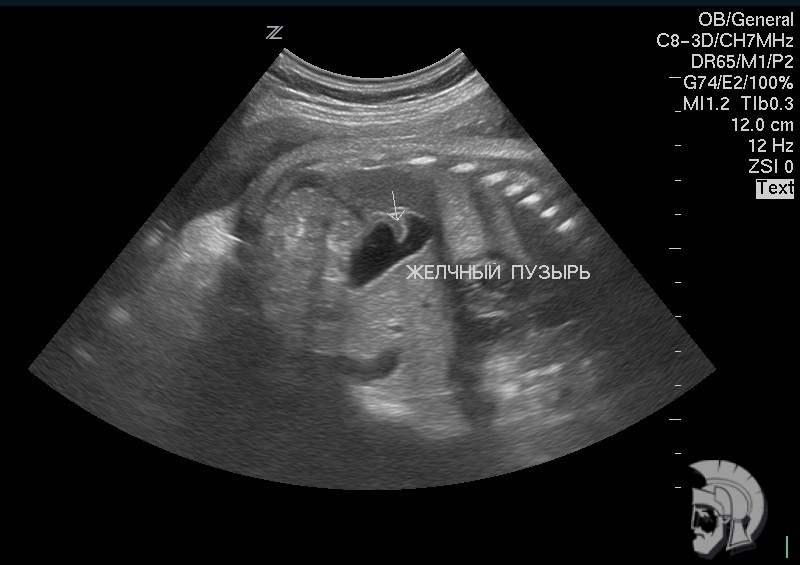

| Фото желчного пузыря. Перетяжка в нижней трети желчного пузыря мужчины 43 лет |

Фото желчного пузыря плода.

Аномалия развития желчного пузыря плода мужского пола 32 недель. Стрелкой указана перетяжка желчного пузыря |